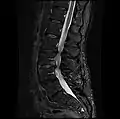

A laminectomy is a surgical procedure that removes a portion of a vertebra called the lamina, which is the roof of the spinal canal. It is a major spine operation with residual scar tissue and may result in postlaminectomy syndrome. Depending on the problem, more conservative treatments (e.g., small endoscopic procedures, without bone removal) may be viable.[1]

The lamina is a posterior arch of the vertebral bone lying between the spinous process (which juts out in the middle) and the more lateral pedicles and the transverse processes of each vertebra. The pair of laminae, along with the spinous process, make up the posterior wall of the bony spinal canal. Although the literal meaning of laminectomy is 'excision of the lamina', a conventional laminectomy in neurosurgery and orthopedics involves excision of the supraspinous ligament and some or all of the spinous process. Removal of these structures with an open technique requires disconnecting the many muscles of the back attached to them. A laminectomy performed as a minimal spinal surgery procedure is a tissue-preserving surgery that leaves more of the muscle intact and spares the spinal process. Another procedure, called the laminotomy, is the removal of a mid-portion of one lamina and may be done either with a conventional open technique or in a minimalistic fashion with the use of tubular retractors and endoscopes.

The reason for lamina removal is rarely, if ever, because the lamina itself is diseased; rather, it is done to break the continuity of the rigid ring of the spinal canal to allow the soft tissues within the canal to: 1) expand (decompress); 2) change the contour of the vertebral column; or 3) permit access to deeper tissue inside the spinal canal. A laminectomy is also the name of a spinal operation that conventionally includes the removal of one or both lamina, as well as other posterior supporting structures of the vertebral column, including ligaments and additional bone. The actual bone removal may be carried out with a variety of surgical tools, including drills, rongeurs and lasers.

The success rate of a laminectomy depends on the specific reason for the operation, as well as proper patient selection and the surgeon's technical ability. The first laminectomy was performed in 1887 by Victor Alexander Haden Horsley,[2] a professor of surgery at University College London. A laminectomy can treat severe spinal stenosis by relieving pressure on the spinal cord or nerve roots, provide access to a tumor or other mass lying in or around the spinal cord, or help in tailoring the contour of the vertebral column to correct a spinal deformity such as kyphosis. A common type of laminectomy is performed to permit the removal or reshaping of a spinal disc as part of a lumbar discectomy. This is a treatment for a herniated, bulging, or degenerated disc.